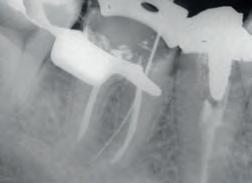

Evaluate the origin of tooth staining and check for restorations that could affect the final result (use X-Ray if needed). Assess the intention of whitening system (cosmetic for generic “day-by-day” discoloration; medical devices for teeth discolored by disease, injury or medical treatment). Consider amending your periodical medical history by adding a question about the patient’s satisfaction with their oral esthetics. Explain to the patient that restorations will not whiten, and discuss the possible need for new restorations after whitening. Check existing sensitivities, and perform an adequate treatment before starting a whitening procedure. Pregnant or breastfeeding women should not whiten. Patients with serious health concerns should consult their primary care provider prior to treatment. Cosmetic teeth whitening treatments are not permited under the age of 18.

Determine origin of staining, evaluate gingival and dental health. Check for restorations in the esthetic zone that may not match after whitening. Discuss changing them out or resurfacing after whitening.